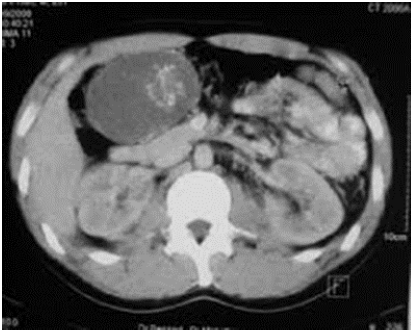

An abdominal CT scan is performed which targets a mass of 9 cm long axis at the expense of the first and second jejunal loop which takes the contrast which remains resectable from the mesenteric vessels (Figure 2). After multidisciplinary consultation, we decided to operate the patient after a preoperative assessment. the patient is admitted to the operating room under general anesthesia, median incision with horse on the umbilicus; the exploration does not find hepatic metastases so the exploration found a mass at the dependence of the 1st and 2nd jejunal loop, one proceeds to a monobloc resection carrying the 2nd handle and a terminal anastomosis is performed, closure without drainage (Figure 3 & 4).